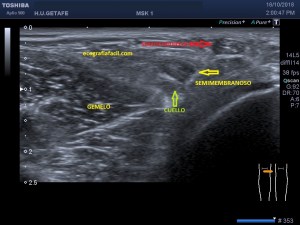

En la imagen 3 ves una imagen de un lipoma, mide 7 cms, la huella de la sonda mide 5cms, la «panoramic view» posee una regla centimetrada que sigue el contorno de la imagen, justo en la profundidad de la misma y lo marca la flecha amarilla. La profundidad la marca la flecha roja y la flecha blanca marca el rango centimetral de los 5cms, fíjate que la línea blanca es ligeramente mayor cada 5 cms. Sirve de referencia, como en la imagen 4 donde ves una colección en el glúteo de más de 10 cms.